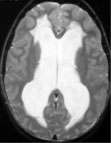

- The diagnosis of hydrocephalus is best confirmed by magnetic response imaging (MRI) of the brain. A computed tomography (CT) scan of the brain can also diagnose hydrocephalus. (But in most cases, an MRI is required afterwards.)

- Hydrocephalus occurs when there is an imbalance between the amount of CSF that is produced and the rate at which it is absorbed. As the CSF builds up, it causes the ventricles to enlarge and the pressure inside the head to increase.